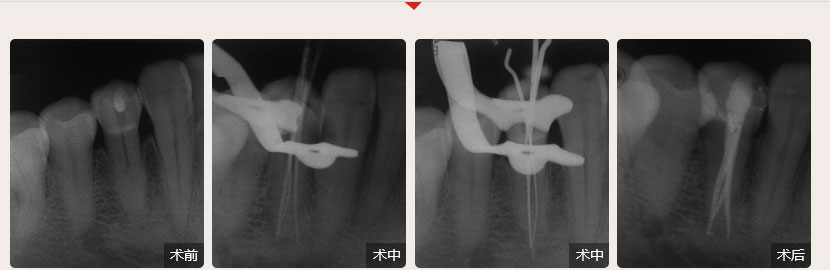

德倫口腔醫生全國根管治療技術競賽獲獎案例展示